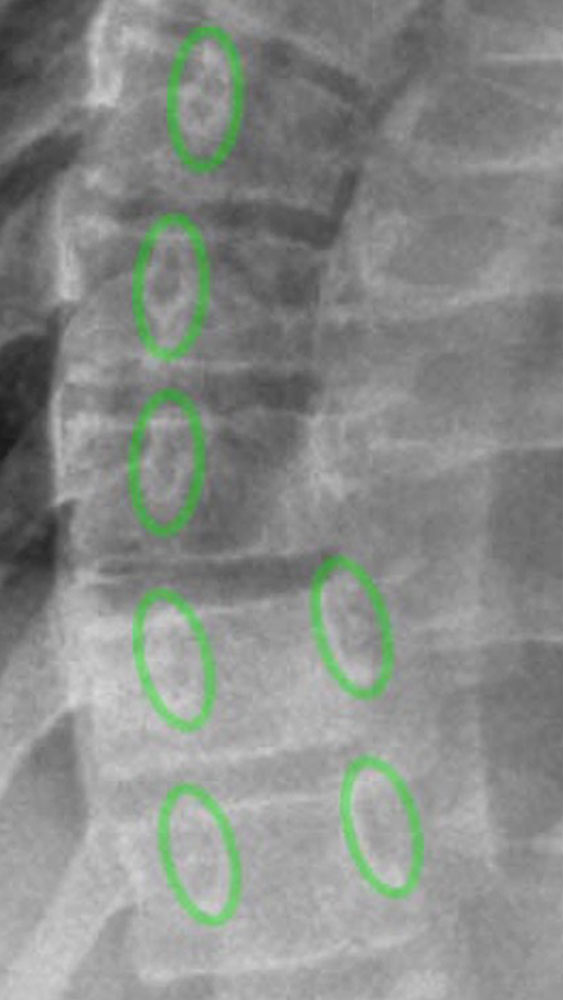

Die Röntgenaufnahme muss ebenfalls stehend und in der Regel als p.a.-Aufnahme der gesamten Wirbelsäule auf einer Röntgenplatte (meist zusammengesetzt) erfolgen.

Hierbei wird der Cobb-Winkel, der Rippenwinkel und die Rotation der Wirbelkörper beurteilt.

Darüber hinaus kann, wenn eine Prognose über die Progredienz der Skoliose gestellt werden soll, das zu erwartende Wirbelsäulenwachstum mithilfe der Beurteilung der Beckenkammapophyse durchgeführt werden (sog. Risser-Stadium). In diesem Fall sollte auf der Ganzwirbelsäulenröntgenaufnahme auch der Beckenkamm abgebildet sein.